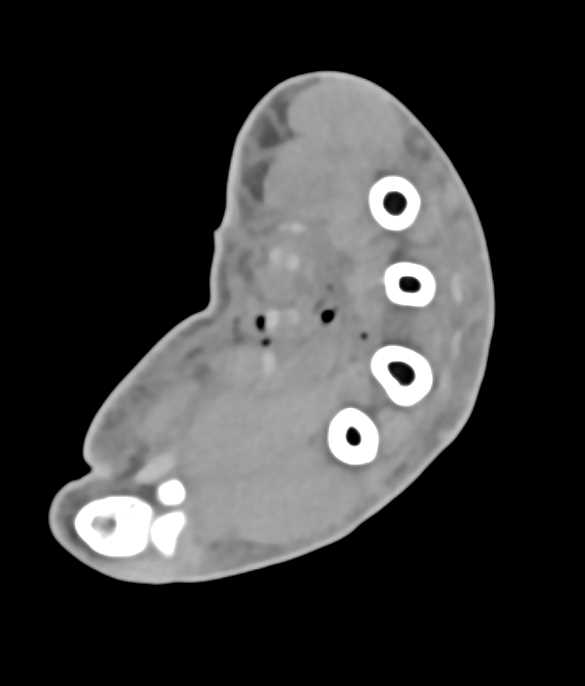

Ulnar Artery Occlusion